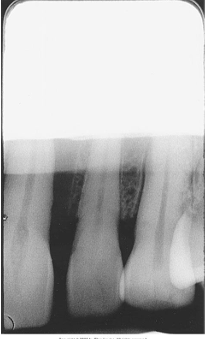

What is the problem with this Underexposed Receptor X-ray?

May occur with digital sensors or film, Image appears light or low density, Receptor was underexpose

How would you resolve this Underexposed Receptor X-ray?

Check exposure time, kilovoltage, and milliamperage settings on the x-ray machine prior to exposing the receptor